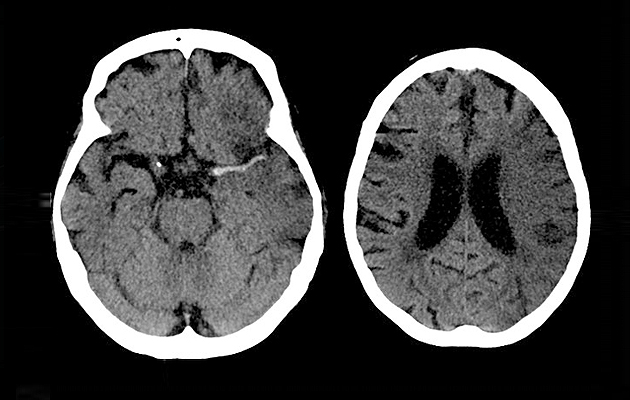

삼성초이스의원 줄기세포 중점 치료분야

알츠하이머

뇌경색